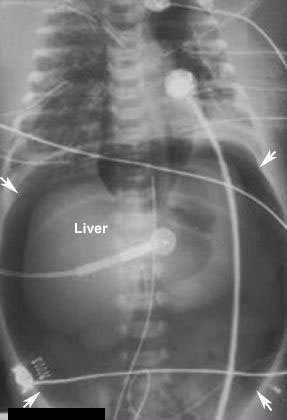

Pneumoperitoneum

Findings:

- Massive - Football sign

- Air collects under the anterior aspect of peritoneal cavity

- L: Liver